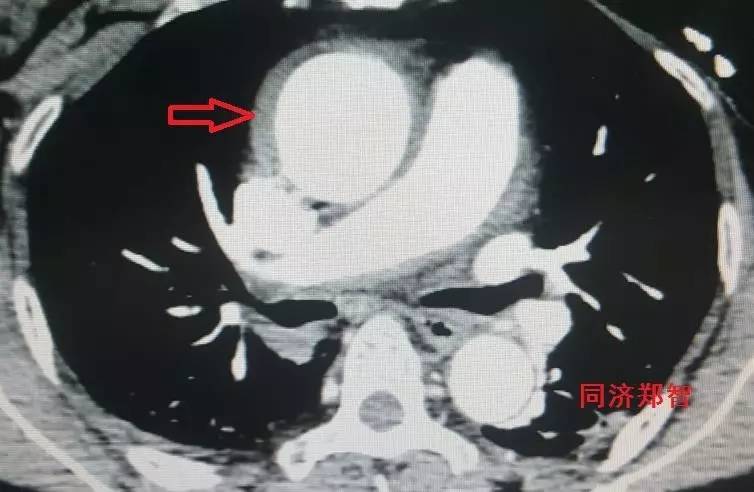

CTA轴位片显示主动脉弓穿透性溃疡(图11)。

图11

三维重建显示主动脉弓穿透性溃疡,与图11为同一病人(图12)。

图12